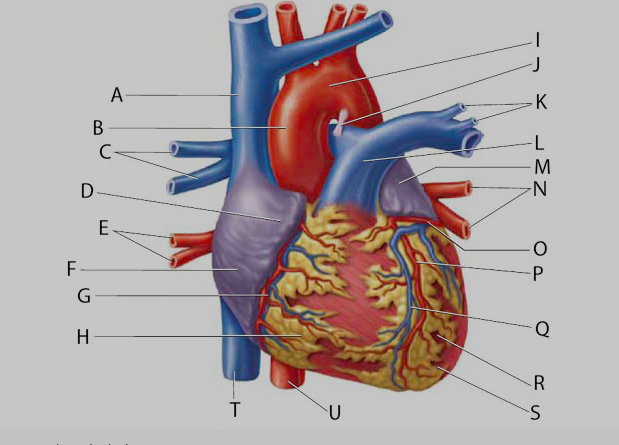

Aortic Arch

Aortic Valve (=left semilunar)

Apex (of the heart)

Brachiocephalic artery

Brachiocephalic vein

Chordae tendineae

Circumflex branch (of the left coronary artery)

Coronary sinus

Endocardium

Epicardium

interventricular branch of the left coronary artery. = left anterior descending artery (LADA))

Left atrioventricular (=bicuspid, =mitral) valve

Left/right atrium

Left/right auricle

Left/right coronary artery

left/right pulmonary artery/vein

left/right ventricle

Myocardium

Papillary muscles

Pectinate muscles

Pulmonary trunk

Pulmonary valve (=right semilunar)

Right atrioventricular (=tricuspid) valve

Superior/inferior vena cava